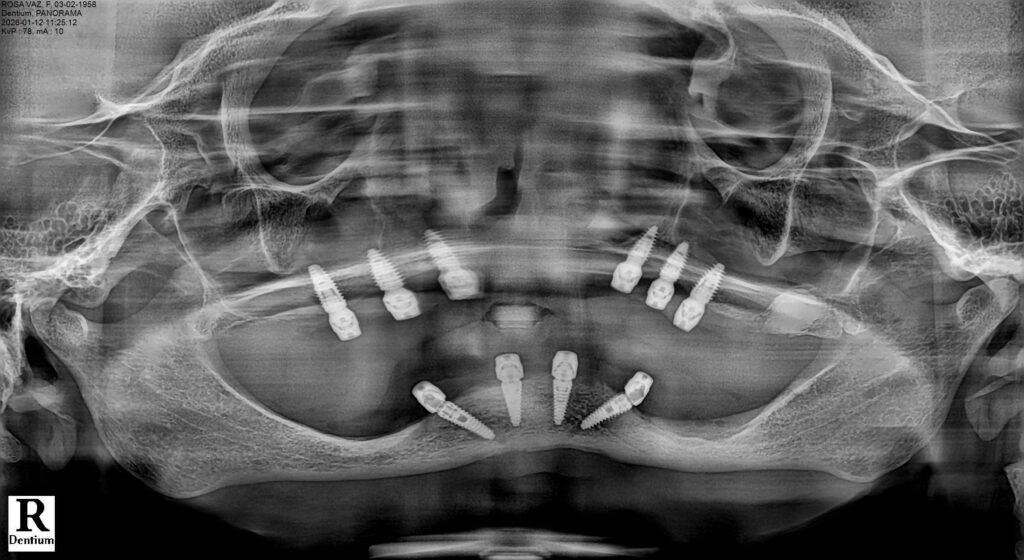

Case presentation: A 75-year-old female patient presented with a fully edentulous maxilla affected by Kelly syndrome, advanced maxillary sinus pneumatization, and reduced bone height and width. The mandible showed an anteriorly positioned inferior alveolar nerve in the premolar regions. Full-arch rehabilitation was performed using an All-on-Six protocol in the maxilla with six straight MegaGen BlueDiamond® implants (Ø 3.3, 3.7, and 4.1 mm) placed using a palatal approach and osseodensification with Densah® burs. The mandible was rehabilitated with an All-on-4 protocol using MegaGen AnyRidge® implants (Ø 3.5 and 4.0 mm).

A full-thickness mucoperiosteal flap was elevated with careful preservation of the palatal soft tissues. Osteotomies were initiated following a palatally shifted trajectory, ensuring parallelism among implants and optimal distribution along the arch. Six straight MegaGen BlueDiamond® implants (diameters 3.3, 3.7, and 4.1 mm) were placed between the canine and first molar regions, avoiding sinus floor perforation and eliminating the need for sinus augmentation procedures.

Implant Placement and Primary Stability

All maxillary implants achieved insertion torque values exceeding 40 Ncm, confirming excellent primary stability and validating the combined use of a palatal approach and osseodensification. Implant platforms were positioned at bone level, with careful attention to prosthetic alignment and emergence.

In the mandible, four MegaGen AnyRidge® implants (diameters 3.5 and 4.0 mm) were placed following an All-on-4 configuration. Posterior implants were tilted to avoid the inferior alveolar nerve and to maximize anteroposterior spread. All mandibular implants also achieved insertion torque values above 40 Ncm, allowing immediate or early loading considerations.